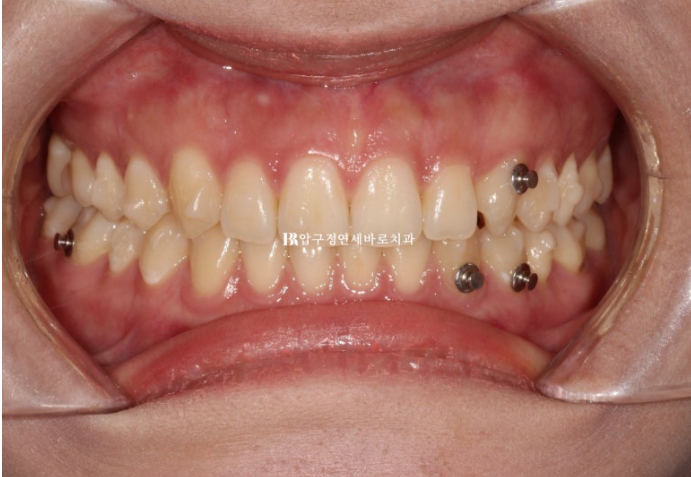

위 아래 중심선이 약 2mm 차이가 나는 상태이고 측절치와 송곳니에 덧니도 보입니다.

24.02

옆에서 보면 가운데 앞니 세개가 뒤로 기울어져 있는 것이 보입니다.

우측은 교합관계가 II급입니다.

앞니 세개가 입천장쪽으로 들어가 있습니다.

웃을 때 앞니가 뒤로 쓰러져 있으면 그림자져 보이고 덜 예쁩니다.

우측 어금니 교합이 II급 교합관계를 보여 정석대로 하자면 타치과 진단대로 어금니를 전체적으로 다 움직이는 1년반 이상의 인비절랑니컴프레헨시브가 필요하겠죠.

하지만 환자분은 기간과 치료의 심플함을 더 중요하게 생각하고 있어서 인비절라인 라이트로 약 9개월 목표로 치료함으로써 중심선과 약간의 교합오차 그리고 약간의 중심선 오차를 허용하는 대신 비용과 기간을 줄이는 것을 택했습니다.

II급 교합관계를 보이는 우측은 고무줄을 끼면서 최대한 I급으로 유도하기로 했습니다.